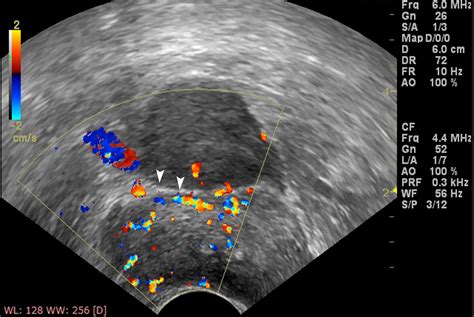

• space of retzius on ultrasound